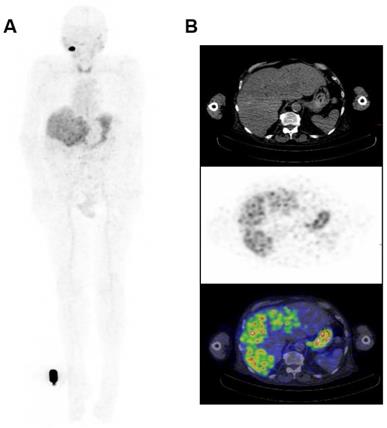

Figure 4

Whole Body Biodistribution of 124I-PEG-AVP0458 (10mg/m2 dose level). (A) Anterior Whole Body PET image on Day 5 in Patient 4. Transaxial images in (B) liver (Upper panel - CT, Middle panel - PET, Lower panel -merged PET/CT) showing excellent uptake of 124I-PEG-AVP0458 in extensive liver metastases of prostate cancer. Whole body images include reference standard by right foot in field of view.

The biodistribution of 124I-PEG-AVP0458 was assessable in 5 of 6 patients, as patient 2 (1 mg/m2 cohort) dose of 124I-PEG-AVP0458 was extravasated and rendering the patient data not evaluable for biodistribution or dosimetry analysis. Figure 2 includes qualitative tumor uptake results for individual patients. Whole body images and representative biodistribution pattern are presented in Figure 3 (1 mg/m2 dose level) and selected transaxial PET/CT sections to highlight metastatic prostate cancer tumor regions are presented in Figure 4 (10 mg/m2 dose level).

124I-PEG-AVP0458 PET imaging showed stable and consistent biodistribution across all patients at both dose levels, with gradual clearance from blood with time, and no significant normal tissue uptake. In particular, no discernible kidney uptake of 124I-PEG-AVP0458 was observed. Tumor uptake was rapid and evident by 1‑2 days post-injection, with sites of metastatic disease in lymph nodes and liver identified. Image-derived time-activity data were used to calculate the median time-integrated activity coefficients (residence time) of 124I-PEG-AVP0458 in all organs and tissues (Table S2). The organ receiving the highest mean absorbed dose was the thyroid gland (2.21 ± 0.61 mGy/MBq). Maximal tumor uptake observed was 12.2 × 10-3 %ID/mL at 7 days. The specific tumor absorbed dose ranged from 1.25 mGy/MBq to 4.75 mGy/MBq (mean ± SD = 2.87 ± 1.49 mGy/MBq), and the measured absorbed tumor dose ranged from 235.88 mGy to 833.06 mGy (mean ± SD = 605.32 + 322.83 mGy).